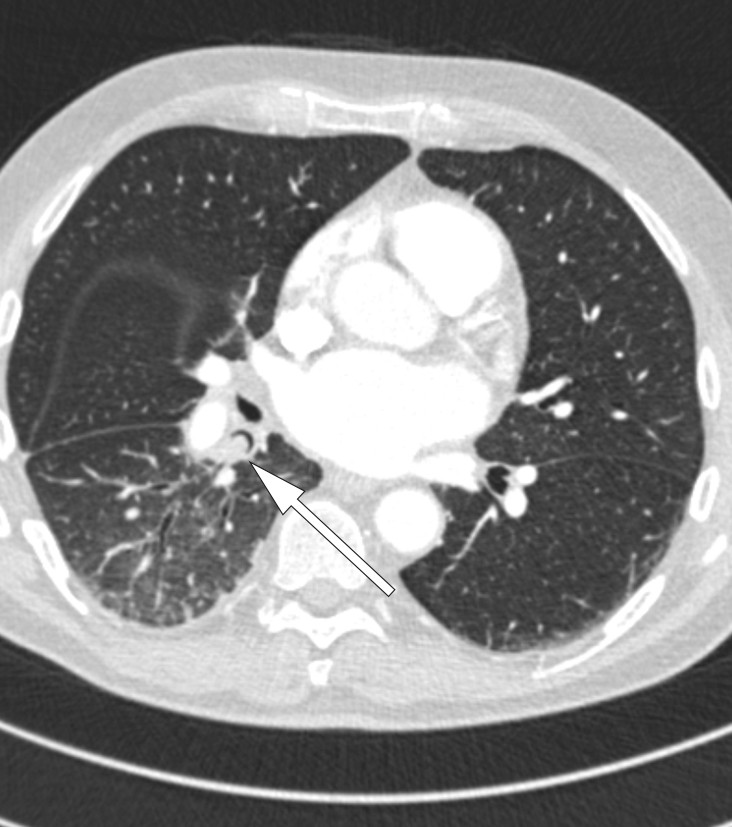

Sykehistorien reiste nå spørsmål om fremmedlegeme, og pasienten ble innlagt i lungeavdelingen for behandling med penicillin intravenøst og videre utredning. Før bronkoskopi ble det utført CT thorax (se CT-bildet) som viste en 8 mm rund forandring proksimalt i høyre underlappsbronkus. Denne ga nær full okklusjon av lumen og forårsaket atelektase av høyre underlapp distalt.

Bronkoskopi ble utført (se endoskopibildet), og en ert ble lokalisert som beskrevet på CT-undersøkelsen og deretter fjernet (se video). Erten var uskadd med en diameter på ca. 10 mm. Pasienten ble feber- og symptomfri i løpet av en kort uke, og røntgen thorax etter åtte uker viste full tilbakegang av atelektasen. Etterkontroll med bronkoskopi var også normal.